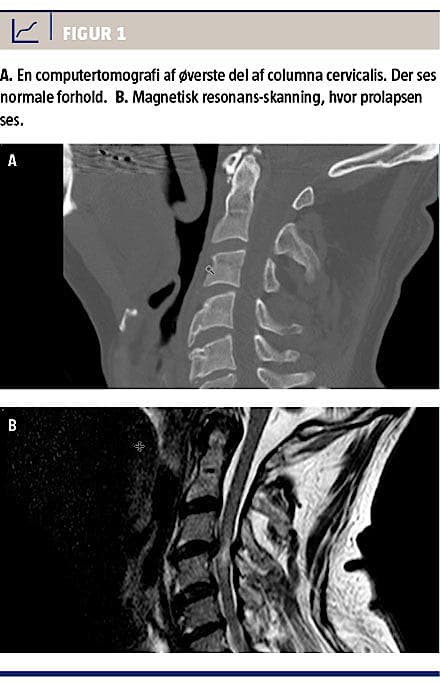

På femtedagen var der ingen fremgang. Neurologerne foreslog magnetisk resonans (MR)-skanning af columna totalis på mistanke om blødning/kontusion. Skanningen blev foretaget på tiendedagen, og den viste, at der var en traumatisk diskusprolaps på C3/C4, hvilket påvirkede medula spinalis (Figur 1).

A 51-year-old male drove into a ditch on his scooter. Immediately after the trauma the patient complained of neck pain and decreased ability to feel and move his extremities. An initial trauma computed tomography (CT) of the columna showed normal conditions. Because the patient had neurological deficiencies, magnetic resonance imaging of the columna was performed 12 days later, and a disc prolapse at the C3/C4 level with spinal cord compression was visible. Despite decompression the patient did not recover. Traumatic cervical disc prolapse is a rare and positionally dangerous condition, which can be present despite a CT showing normal conditions.